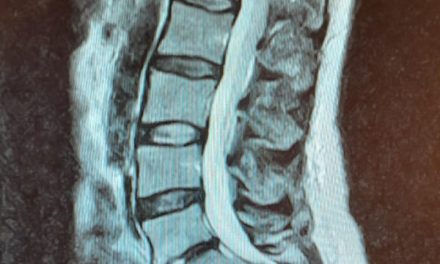

Een paar weken later bekijken we samen de beelden van de echo. Onzeker scrollen we door de foto’s heen, niet echt wetende waar we op moeten letten. En dan zien we het: Een enorme witte bal, op de plek waar je de blaas en de baarmoeder zou verwachten. “Is dat mijn baarmoeder?” Ik weet niet zo goed wat ik moet antwoorden. “Nee, wacht, fucking hell, dat is dat ding.”

Dat ‘ding’ is een tumor. Geen kanker, gelukkig, maar wel degelijk een tumor. Met een omvang van zo’n tien centimeter; zo groot als een honkbal dus. Dat ‘ding’ dat haar baarmoeder, eierstokken, blaas en al het andere dat er nog zit volledig wegdrukt. Geen wonder dat ze constant pijn heeft.

De witte bol in het midden valt moeilijk te missen.